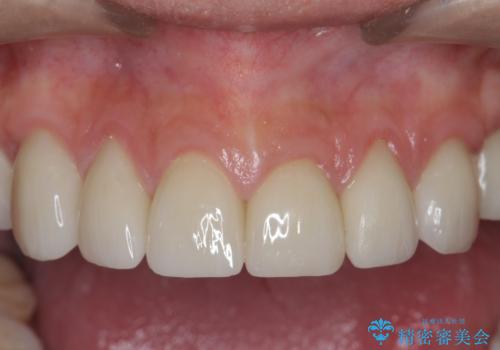

神経を温存したまま仮歯に置き換え、噛み合わせの安定を確認したのちに すり減りに強いジルコニアクラウンで最終的な仕上げを行います。

- 145.2万円(仮歯・ジルコニアクラウン×12歯)費用は治療当時の料金となります

歯の形態・色調を大きく変更する場合ジルコニアクラウンによる治療が耐摩耗性・審美性の観点から推奨されます。